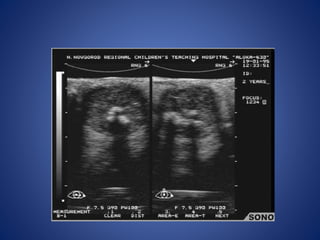

• #17 Retinal hemorrhage in a boy less than 1 year old who presented with trauma. - fluid-fluid level